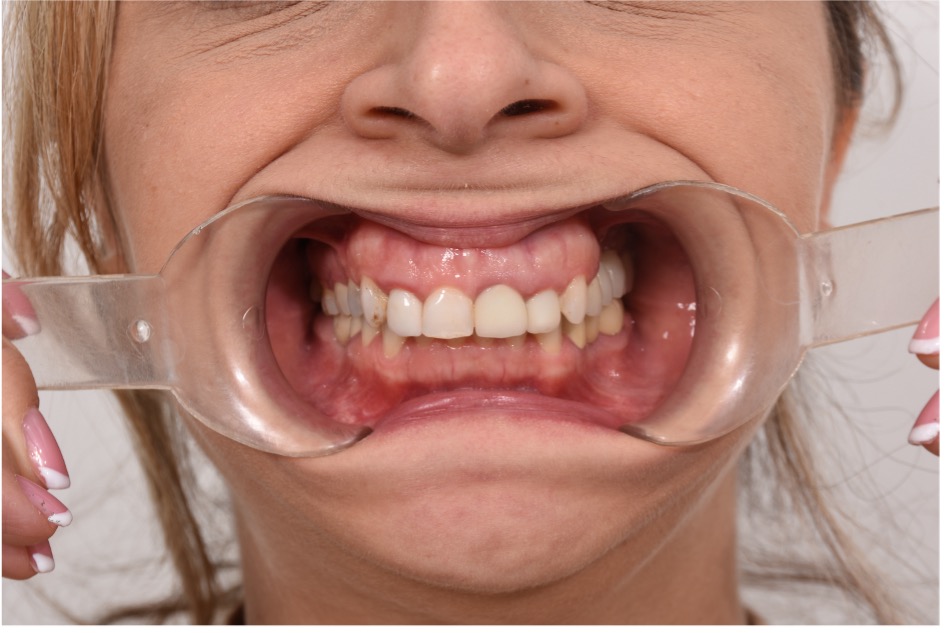

• Chief Complaint: Gummy Smile and Old Crowns

• Initial Diagnosis: Excessive Gummy Smile and Discolored old crowns

Step 1: Diagnostic Assessment and Smile Design The treatment began with a comprehensive evaluation of the patient’s smile using facially guided diagnostics. The Facial Flow Concept was employed to assess the relationship between the patient's facial structure, lips, smile arc, and gingival display. SmileFy software was utilized to generate a 2D digital smile simulation.